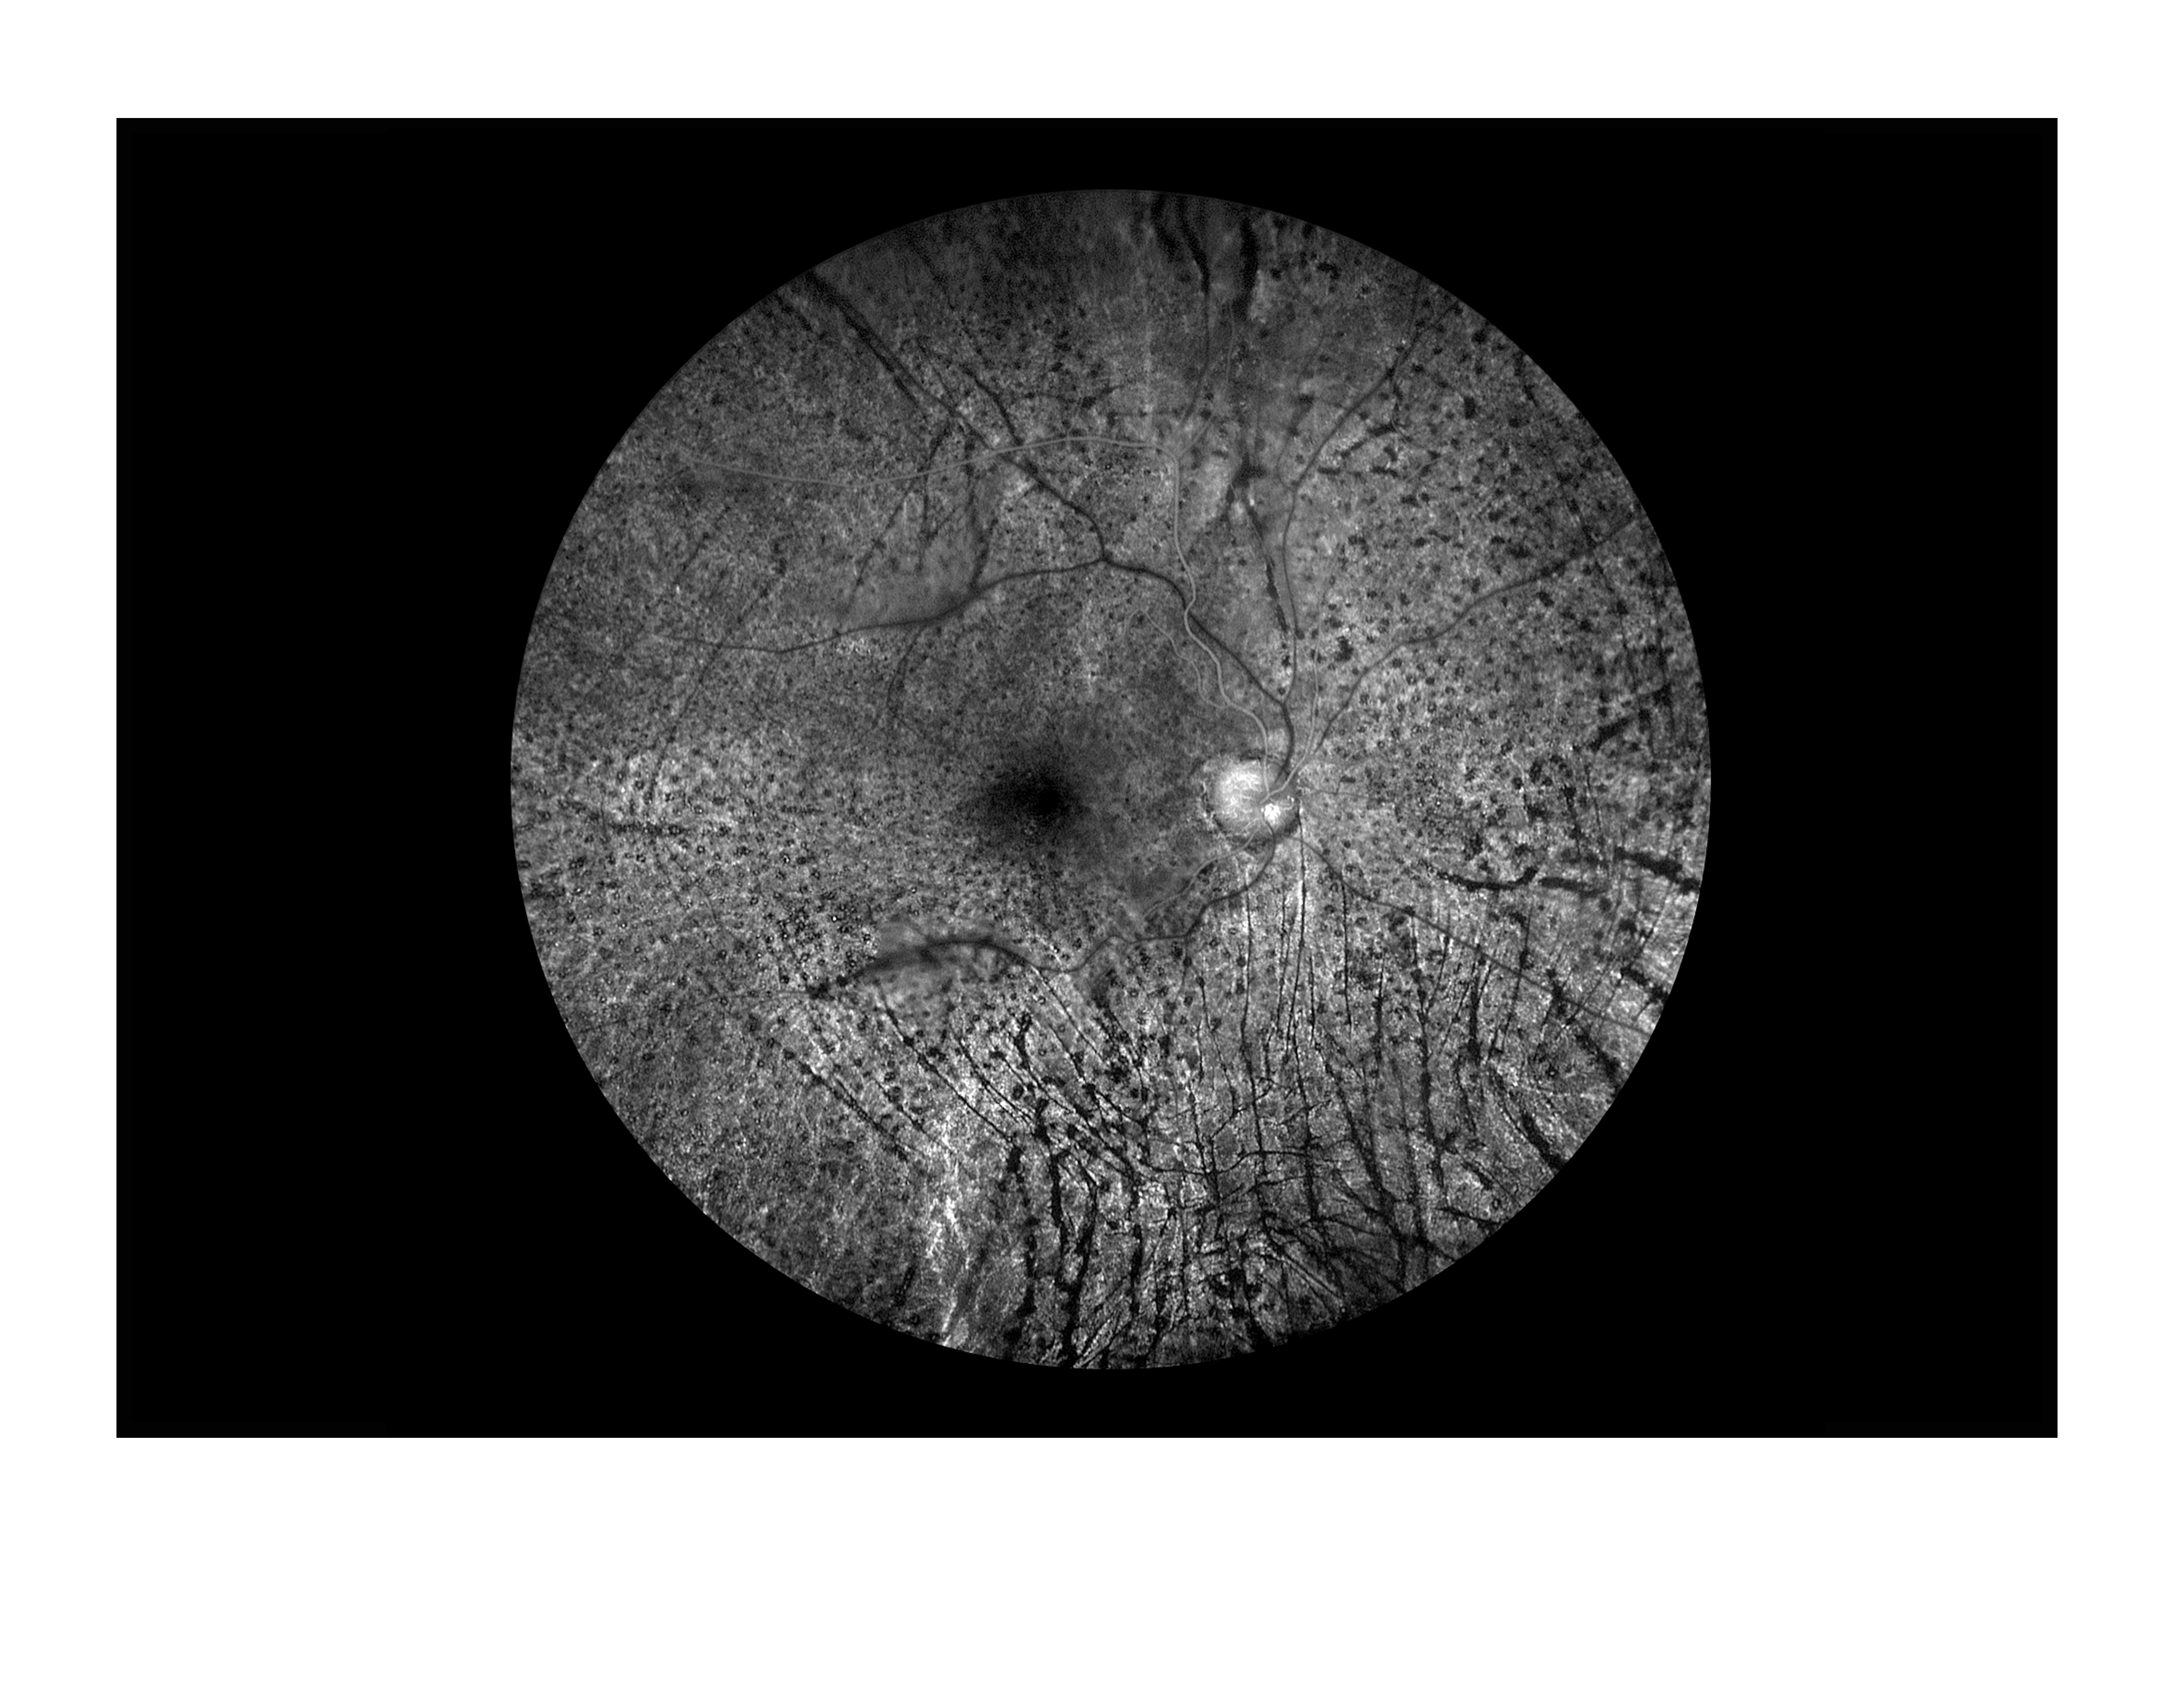

Untitled Presented by Becky Weeks, CRA, OCT-C This photograph received Second Place in the category "Fluorescein Angiography" and was displayed in the 2024 OPS Exhibit. Filed Under Retina OPS Photo